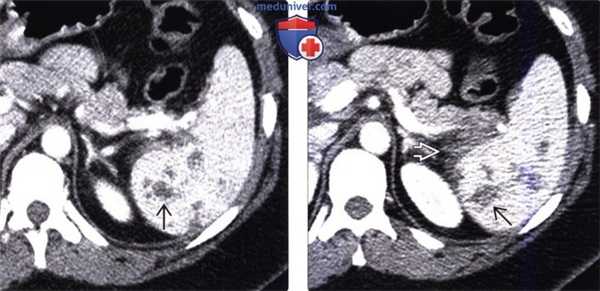

(Слева) На аксиальной КТ с контрастным усилением у женщины 39 лет, получившей множественные травмы в ДТП, в селезенке определяются многочисленные участки вытянутой и неправильной формы, не накапливающие контраст.

(Справа) На аксиальной КТ с контрастом у этой же пациентки (типичный случай разрыва селезенки) также определяются участки пониженного накопления контраста в селезенке, визуализируется небольшая гематома возле ее края.